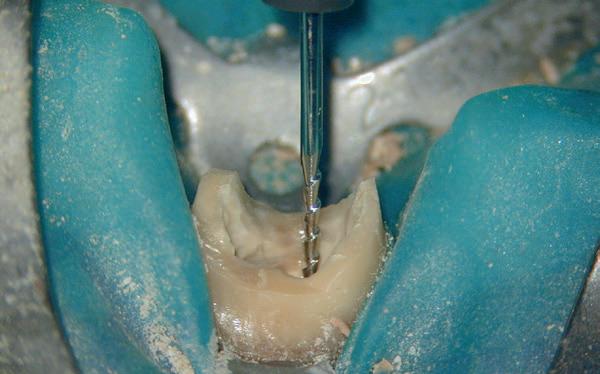

Aangezien dit zou kunnen duiden op een crack of fractuur, wordt besloten om het element te openen en te inspecteren.

Na het verwijderen van de opbouw blijken er geen tekenen te zijn die op een crack of fractuur duiden, en dus gaan we verder met het verwijderen van de

5: Hedström vijl is ingebracht naast zilverstift sectie

6: Zilverstift sectie verwijderd

Voor het verwijderen van zilverstiften zijn verschillende technieken beschikbaar, en de behandelpro-

cedure kan variëren van heel simpel tot zeer lastig. Allereerst moet de zilverstiftsectie blootgelegd en zichtbaar gemaakt worden. Met een geschikt oplosmiddel zoals chloroform wordt in combinatie met handvijlen en/of ultrasone vijlen de cementlaag rondom de zilverstift gedesintegreerd, waardoor de zilverstift na verloop van tijd losser in het kanaal zit. Tot slot moet de losgemaakte zilverstift worden verwijderd. We gebruiken hiervoor bij voorkeur een Hedström vijl en een naaldvoerder.

Nadat het omgevende cement zoveel mogelijk is verwijderd, wordt geprobeerd om naast de zilverstift een plek te vinden waar met dunne handvijlen zo ver mogelijk naar apicaal kan worden geprepareerd. Het gebruik van een operatiemicroscoop is hierbij onmisbaar. De ontstane ruimte tussen zilverstift en kanaalwand kan dan gepenetreerd worden met een Hedström vijl (afbeelding 5). Het doel is om de Hedström vijl met een aantal voorzichtige schroefbewegingen met de klok mee in de zachte zilverlegering te laten grijpen.

Als de Hedström vijl goed vastzit in het zilver, wordt met een naaldvoerder die net onder het handvat wordt geklemd de zilverstift uit het kanaal geheveld (afbeelding 6). Een buurelement fungeert hierbij als steunpunt. Er dient tijdens de hele procedure veelvuldig te worden geïrrigeerd met natriumhypochloriet, om te voorkomen dat er tijdens het instrumenteren corrosieproducten van de zilverstift door de